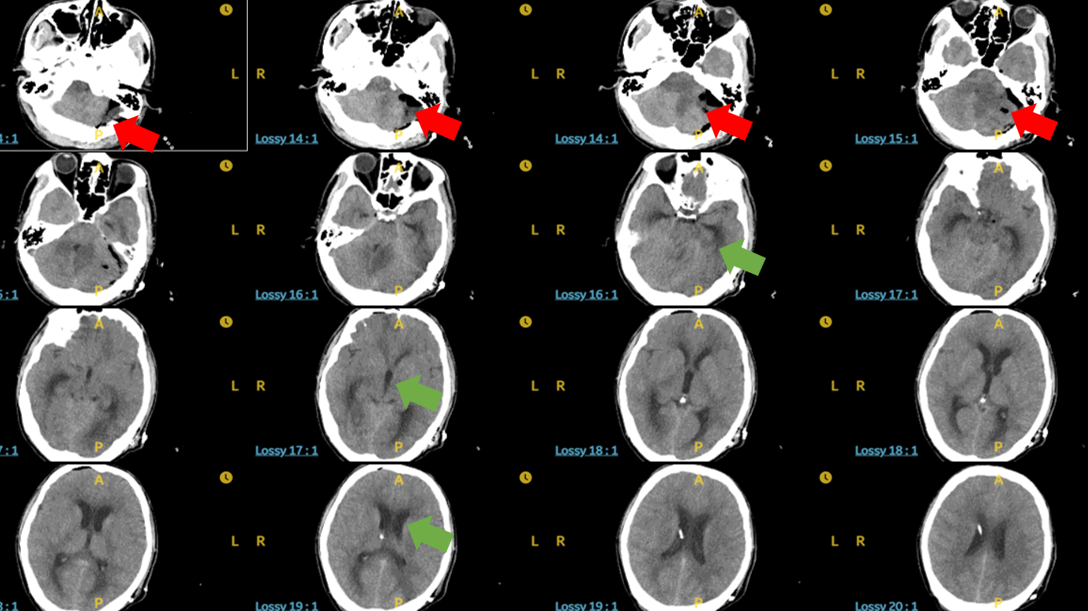

图2术前头颅CT:红色箭头示巨大脑内血肿,

绿色箭头是脑积水导致幕上脑室系统扩张,脑组织受压

图4术后头颅CT:红色箭头示脑内血肿被完全清除,

绿色箭头是脑积水明显缓解,幕上脑室系统恢复,脑组织受压改善